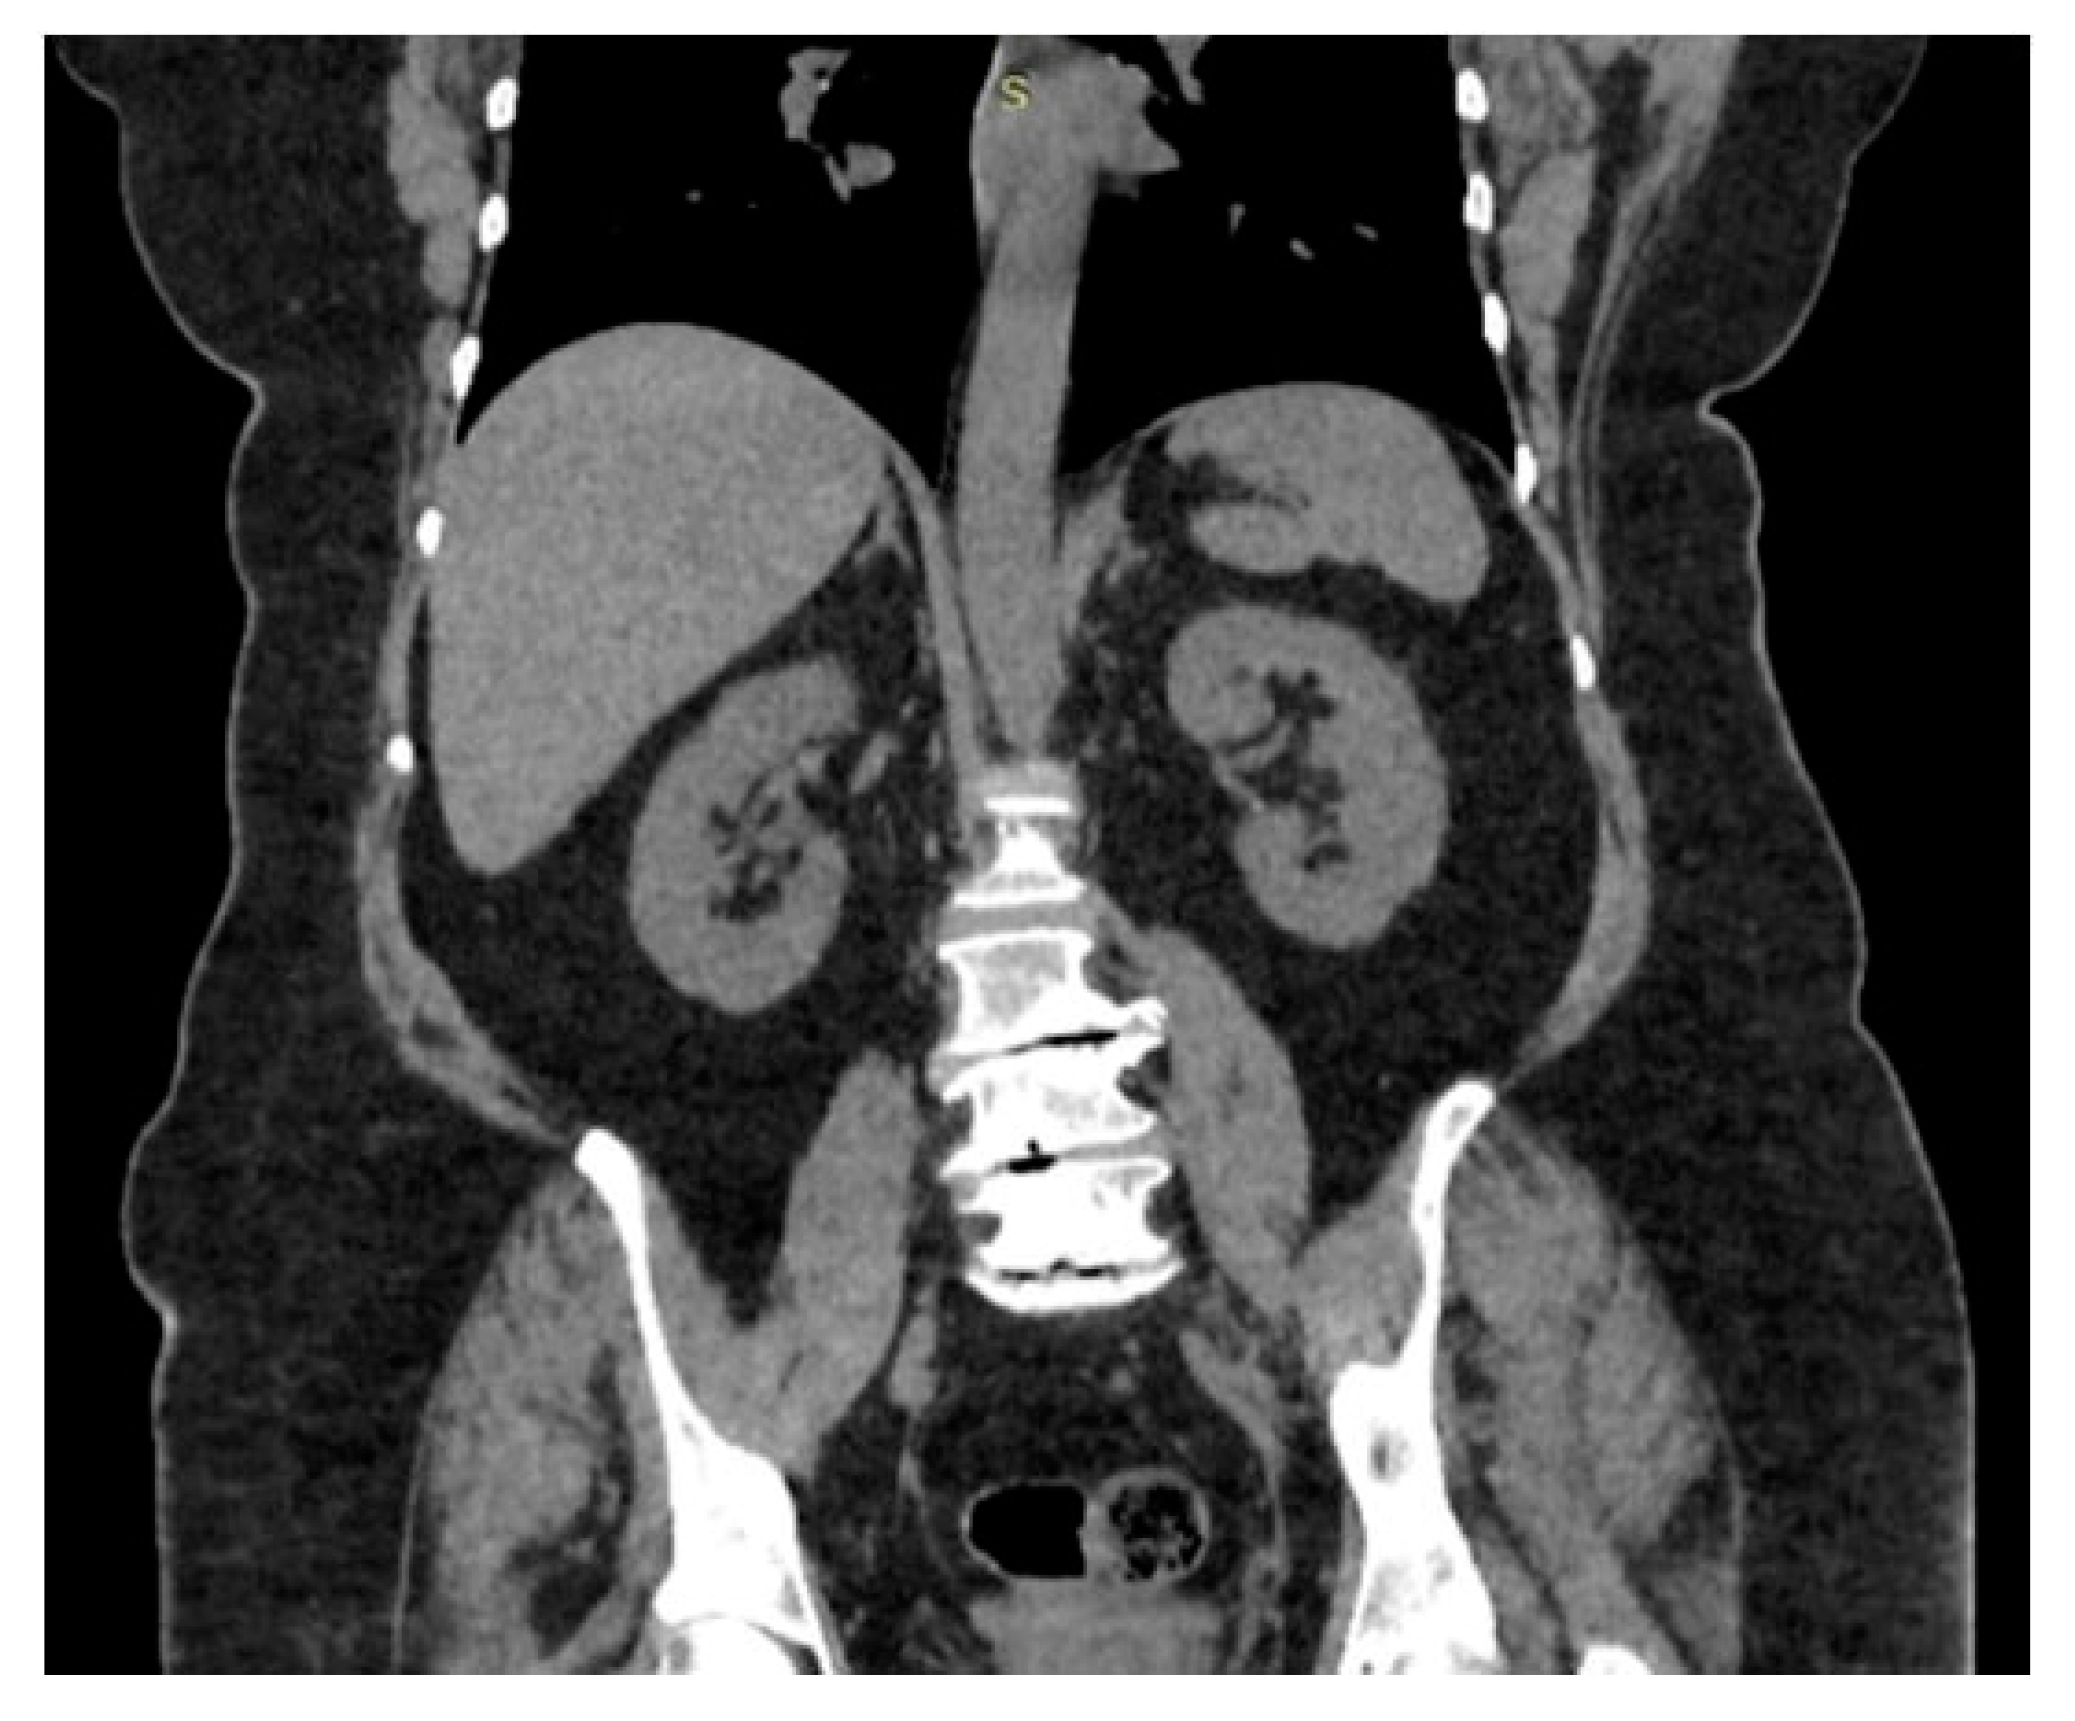

3.2. Clinical Case